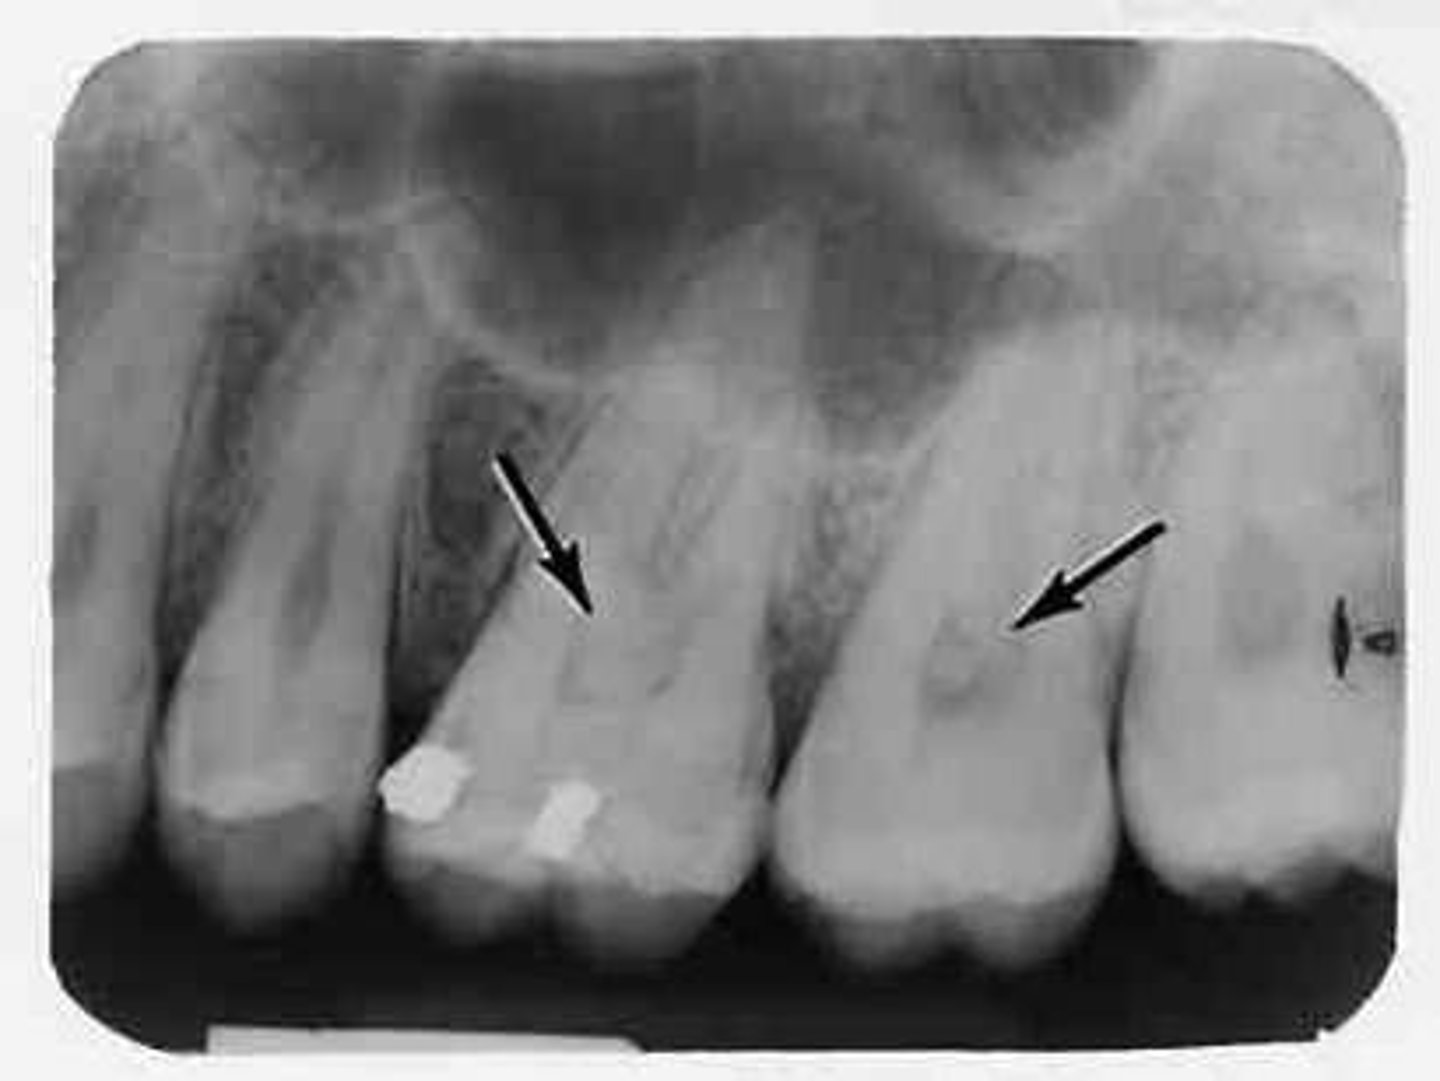

Why are pits bad?

-incomplete fusion of enamel in deep pits

-nearly impossible to clean

-prime location for decay (pit and fissure caries)